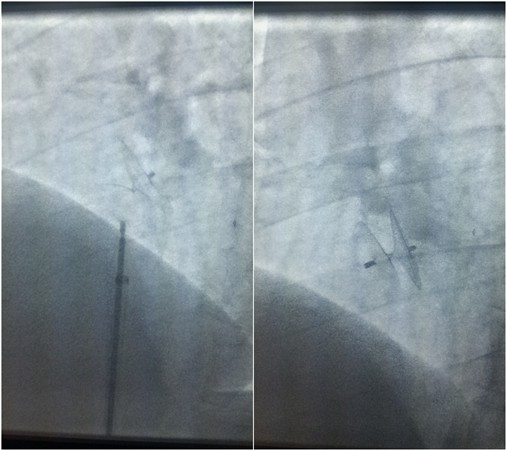

神经内科张茹教授、心血管外科裴斐教授、超声科刘保民教授针对上述病例进行会诊讨论,认为依据国内外目前共识,患者不明原因的头痛、头晕症状以及反复发作的脑卒中可能与PFO所致反常栓塞相关,可试行PFO封堵术。经充分沟通,苦苦求医的2名患者及其家属重燃希望,积极要求行手术治疗。经术前充分准备,心血管外科相里伟、万俊哲、张伟团队在裴斐教授带领下与超声科刘保民教授合作,先后于2015年12月21日及12月31日进行了两例PFO封堵术,手术过程顺利。术后复查心脏彩超及右心声学造影,结果提示“房水平静息与负荷状态下均未见右向左分流”。2例手术患者术后恢复良好,前者无头痛、头晕发作,后者无新发脑卒中,均已顺利出院,定期随访。

手术进行中

卵圆孔封堵器释放后